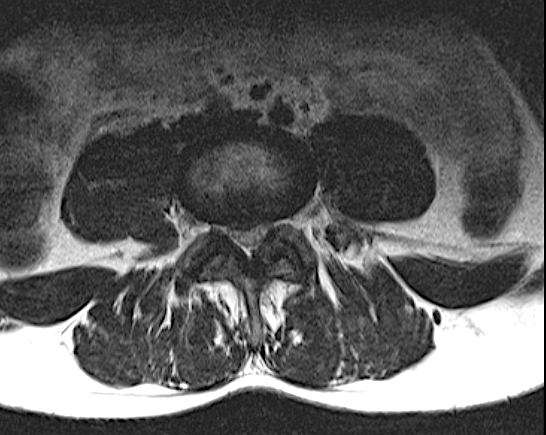

–Microcirugía lumbar: el uso del microscopio quirúrgico permite incisiones mínimas con resultados muy contrastados a largo plazo en la Discectomía lumbar. La «microdiscectomía» no sólo sigue estando vigente para el tratamiento de la hernia discal sino que sigue siendo técnica gold standard (técnica de elección). Sin embargo, el desarrollo de la instrumentación actual, además de minimizar el daño en la musculatura y lograr descompresiones satisfactorias, facilita la fusión con técnicas como el TLIF MIS o la fijación transfacetaria + injerto intersomático.

En el TLIF MIS (Transforaminal Lumbar Interbody Fusion Minimal Invasive Surgery) se obtiene el mismo resultado que el TLIF clásico o abierto, con la diferencia que sólo se realizan dos incisiones paramedianas y no se separa la musculatura de sus anclajes osteoligamentosos. El postoperatorio es mucho mejor en el TLIF MIS que en una cirugía abierta, sin embargo muchas veces no se puede plantear TLIF MIS y hay que realizar TLIF «abierto», sobre todo en patología degenerativa avanzada cuando vamos a asociarlo con otras técnicas (Laminectomía lumbar o artrectomía bilateral para corrección de lordosis o listesis).

La Fijación transfacetaria lumbar puede usarse como técnica de fusión MIS en la Discectomía lumbar, asociando un injerto intersomático. También puede tener su utilidad como complemento del TLIF MIS en el lado percutáneo. La orientación, tamaño e integridad de las facetas así como la ausencia de subluxación limita, en mi opinión, un uso más generalizado de esta técnica.